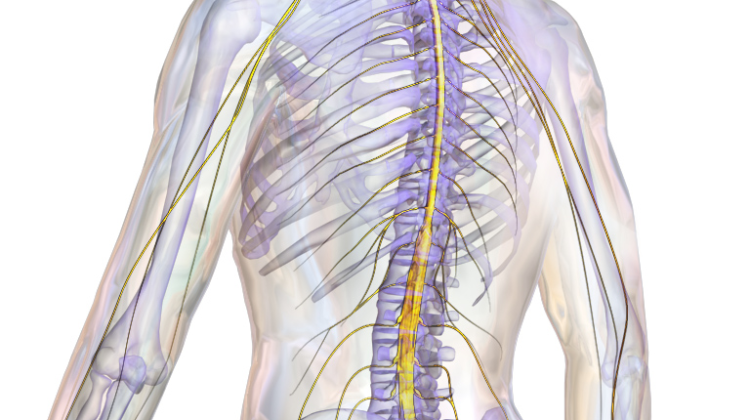

فهم دور الحبل الشوكي في تصحيح اعوجاج العمود الفقري

عند محاولة تصحيح اعوجاج العمود الفقري، يجب التغلب على جميع القوى المقاومة للانحناء. بعض المقاومة تأتي من الأربطة القصيرة والمتشددة والعظام غير المتماثلة، وهذه يمكن تعديلها أو قصها أثناء الجراحة. لكن هناك قوة واحدة لا يمكن تعديلها: الحبل الشوكي.

الحبل الشوكي يمتد داخل قناة العمود الفقري، وعند محاولة جعل العمود الفقري مستقيمًا، يُصبح طول القناة أكبر، مما يؤدي إلى شد الحبل الشوكي. إذا حاول الجراح جعل العمود الفقري مستقيمًا بالكامل، فإن شد الحبل الشوكي قد يؤدي إلى شلل دائم عند بعض الأطفال.

في العقود السابقة، كان الشلل الناتج عن تصحيح الانحناءات الزائدة مشكلة شائعة في جراحات دمج العمود الفقري لعلاج الاعوجاج. ولتفادي هذه المخاطر، أصبح من الروتين مراقبة الحبل الشوكي أثناء الجراحة، لضمان عدم تمديده أكثر من طاقته. وهذا يعني أن الجراح يحتاج إلى تقييد مدى التصحيح حسب قدرة الحبل الشوكي على التحمل.